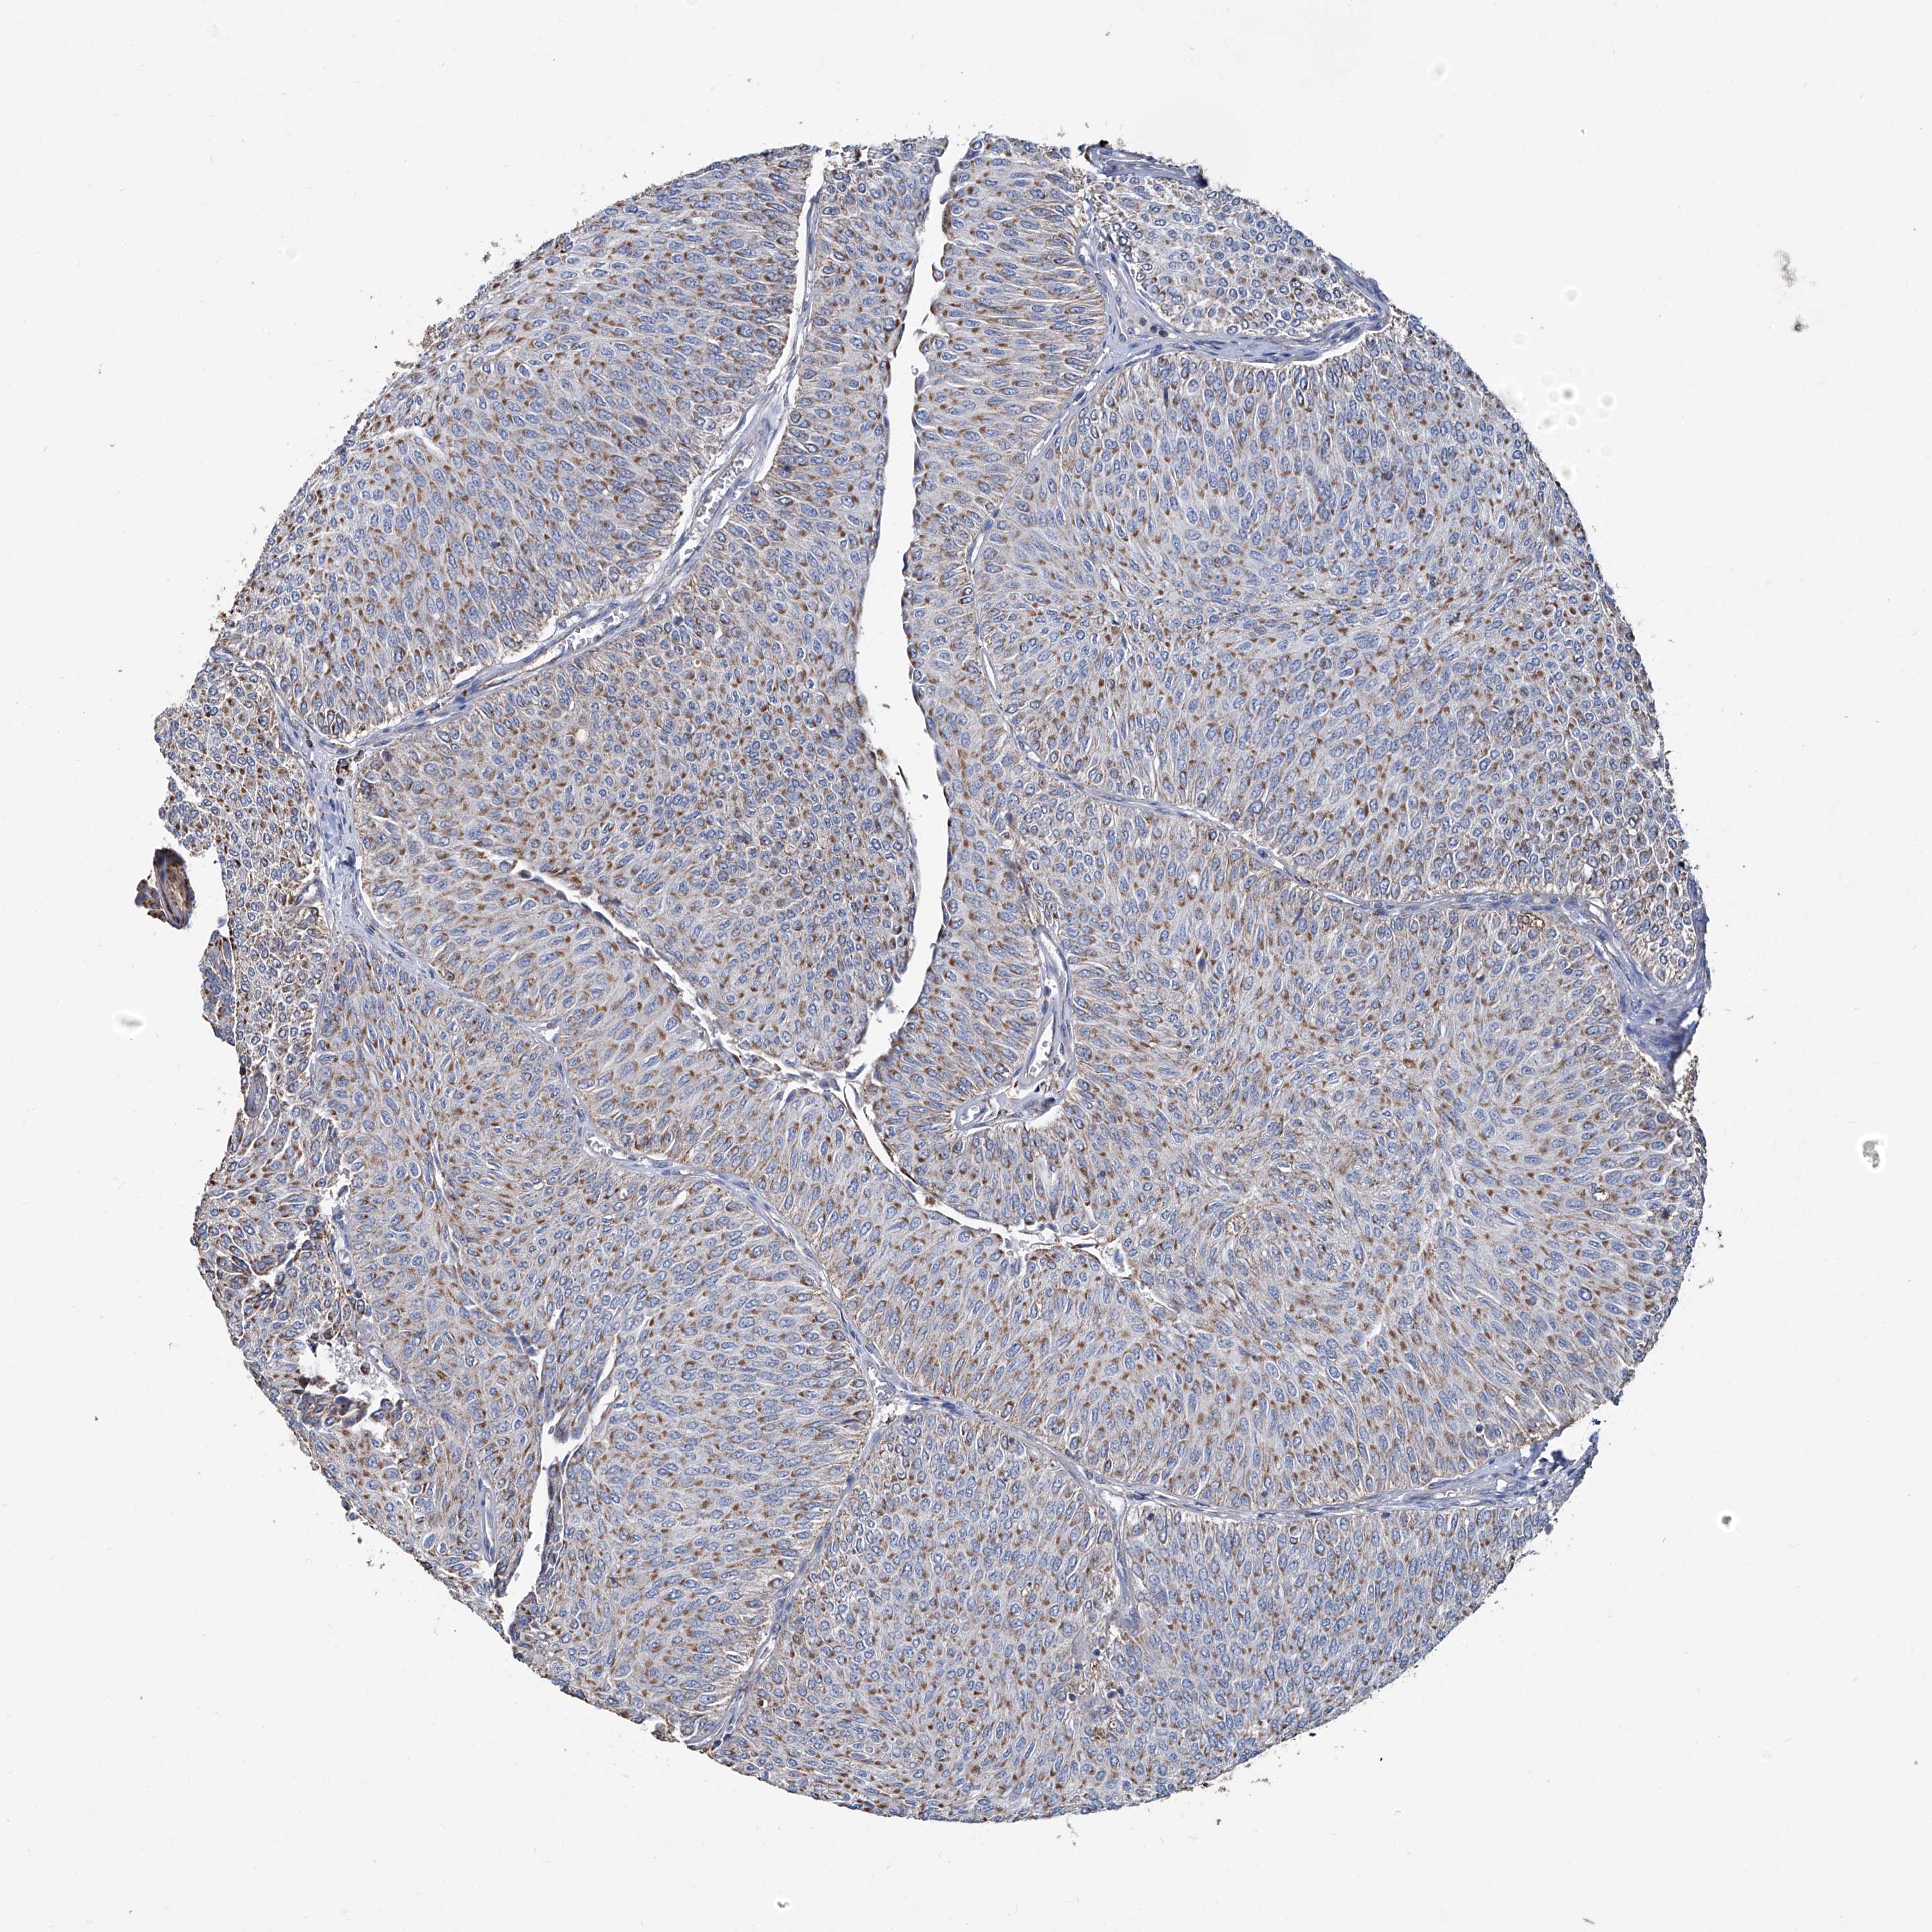

UROTHELIAL CANCER - Protein expressioni

A mouse-over function shows sample information and annotation data. Click on an image to view it in a full screen mode. Samples can be filtered based on level of antibody staining by selecting one or several of the following categories: high, medium, low and not detected. The assay and annotation is described here.

Antibody stainingi

Antibody staining in the annotated cell types in the current human tissue is reported as not detected, low, medium, or high, based on conventional immunohistochemistry profiling in selected tissues. This score is based on the combination of the staining intensity and fraction of stained cells.

Each image is clickable and will lead to virtual microscopy that enables deeper exploration of all samples and also displays staining intensity scores, fraction scores and subcellular localization as well as patient and tissue information for each sample.

Antibody HPA031497

Staining

High

Medium

Low

Not detected

Intensity

Strong

Moderate

Weak

Negative

Quantity

>75%

75%-25%

<25%

None

Location

Nuclear

Cytoplasmic/membranous

Cytoplasmic/membranous,nuclear

Urothelial carcinoma, Low grade

Urothelial carcinoma, High grade